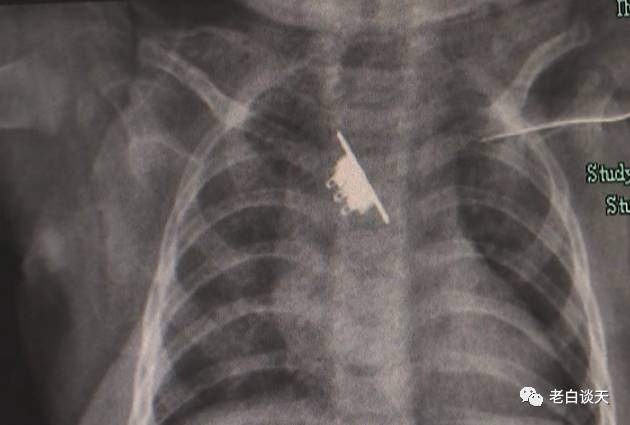

| Để con tự chơi, bé gái khóc thét, nôn ra máu, kết quả X-quang khiến cả nhà suy sụp. |

Phim chụp X-Quang cho thấy có một dị vật nằm trong cổ họng của bé gái. Nhưng các bác sĩ cho biết thêm đó chỉ là một phần, một phần khác không xuất hiện trong bức ảnh mà đang mắc kẹt ở thực quản. Thực quản của trẻ rất mỏng có thể gây ra nhiều tổn thương, thậm chí là rách thực quản, nguy hiểm hơn rất nhiều so với người lớn.

Sau khi họp khoa nội soi, khoa gây mê, khoa nhi và các khoa khác, các bác sĩ quyết định làm phẫu thuật luôn. Thật may, dị vật đã được gắp bỏ hoàn toàn sau nỗ lực của cả ê kíp. Đó là phần công tắc của đèn pin. Bé gái tiếp tục được theo dõi 2 ngày sau đó để kiểm tra tình hình sức khỏe.